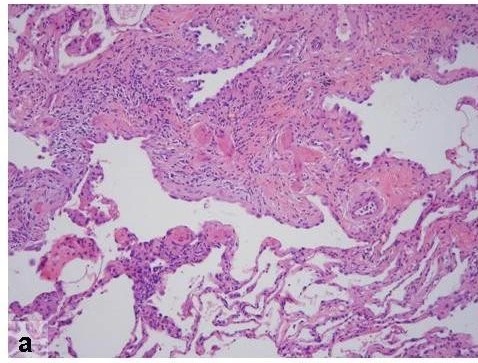

The chief diagnostic criterion of UIP is patchy dense fibrosis at low magnification.5

UIP shows alternating areas of patchy pulmonary parenchymal fibrosis with scarring and honeycomb changes and less affected or normal parenchyma.57,58

Histopathologic features of usual interstitial pneumonia. Reprinted from Fishman's Pulmonary Diseases and Disorders, 4th edition 2007. Meltzer, EB and Noble, PW: Chapter 70, Idiopathic Pulmonary Fibrosis. Used with permission from McGraw-Hill Companies, Inc. Copyright © 2007 McGraw-Hill Companies, Inc.10

Histopathologic changes in IPF often affect the subpleural and paraseptal parenchyma most severely.5,17

The involved areas of the lung show complete distortion of normal architecture, with sheets of dense collagen replacing normal lung tissue and occasional microscopic honeycomb cysts.10